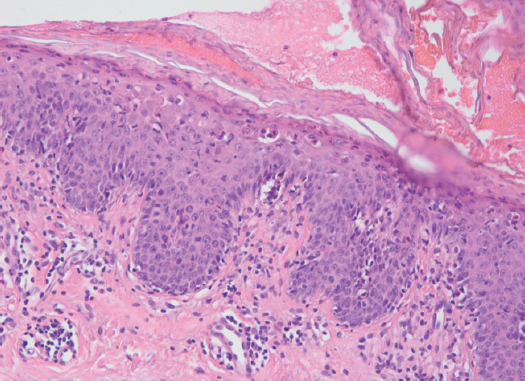

Эритродермия — сравнительно малоизученное угрожающее жизни состояние, характеризующееся диффузной гиперемией и шелушением всего кожного покрова. Среди причин эритродермии выделяют прогрессирование хронических дерматозов, рефрактерных к проводимой терапии, прием лекарственных препаратов или неадекватное местное лечение дерматозов. Кроме того, она может являться симптомом и/или признаком системных заболеваний (лимфома, лейкемия, опухоли легких, кишечника и яичников). Большинство описанных в литературе случаев эритродермии были индуцированы приемом различных видов лекарственных средств и биологически активных добавок. Высокая летальность данной категории больных связана как с основным заболеванием, послужившим причиной развития эритродермии, так и с характером возникающих метаболических расстройств. Эритродермия представляет собой одно из самых тяжелых состояний, угрожающих жизни больного, требующих особых подходов в диагностике и скорейшем начале лечения. При постановке диагноза и определении форм эритродермии одним из определяющих факторов выступает клинический осмотр и клинико-патологическая корреляция. Пациенты с заболеваниями пищеварительного тракта имеют высокий риск развития побочных эффектов от приема лекарственных препаратов и проведения инструментальных методов исследования. Одним из скрининговых методов исследования является фиброгастродуоденоскопия (ФГДС). Приводим описание первого в своей практике случая больного эритродермией, возникшей после ФГДС-исследования. Также в статье обсуждены вопросы патогенеза, дифференциальной диагностики эритродермии на основании клинической картины и гистологических признаков.

- Заславский Д.В., Чупров И.Н., Насыров Р.А., и др. Гистологические модели (паттерны) воспаления при эритродермии // Иммунопатология, аллергология, инфектология. - 2016. - № 4. - С. 65-73. [Zaslavsky DV, Chuprov IN, Nasyrov RA, et al. The histological patterns of inflammation in erythroderma. Immunopatologiya, allergologiya, infektologiya. 2016;(4):65-73. (In Russ.)]. doi: 10.14427/jipai.2016.4.65.